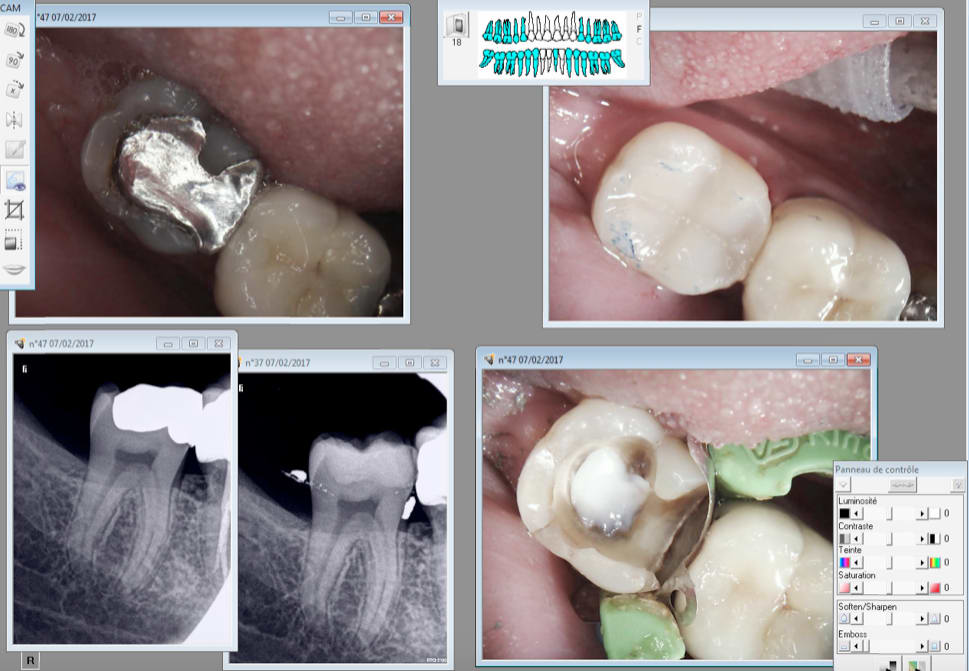

07/02/2017 à 19h17

Re essai bulk fill estelite flow

Capture d écran 2017 02 07 19.15 - Eugenol